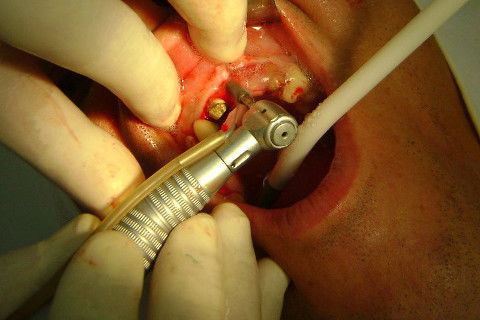

Cirurgia realizada hoje de manhã...No planejamento percebi medindo espessura do rebordo com especímetro que as medidas não estavam muito boas, ou o ideal, em torno de 4,5 a 5 mm ate´o terço médio do rebordo e melhorava no final, com 6 a 7 mm. Optei então por uma pequena expansão usando os expansores rosqueáveis. Aconteceu uma pequena fenestração na hora da fixação dos implantes, especialmente na região do 22 que fraturou o início da tábua óssea, mas não me preocupei porque não foi mais do que 2 mm de fratura em direção apical, o implante ficou infraósseo e com boa estabilidade (60 N no 21 e 40 N no 22). Esta fratura tb não deixou osso completamente solto, foi do tipo galho verde, deixei em posição e suturei normalmente. Só não fiz e nem estava planejado carga imediata mesmo, mais pelo motivo da oclusão inadequada do caso.